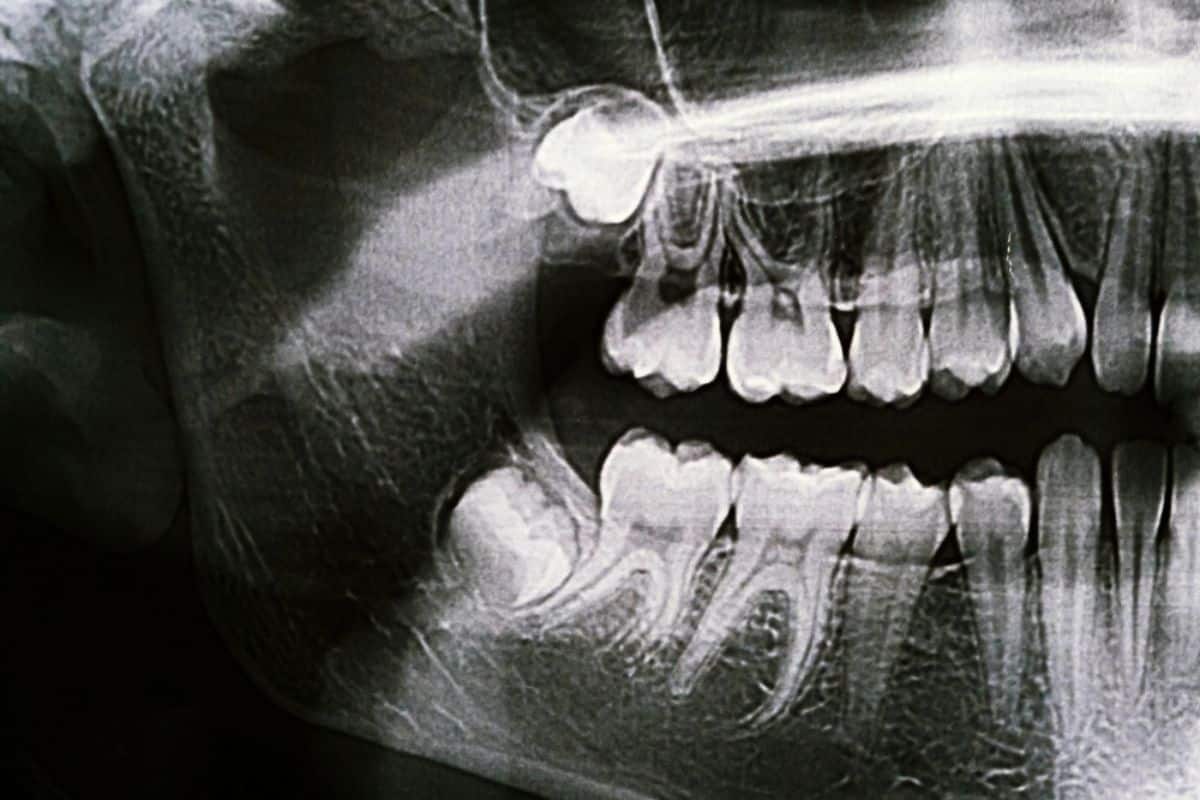

Wisdom teeth are the last set of molars that typically emerge in your late teens or early twenties. When these teeth do not have enough room to grow in properly, they become impacted, meaning they grow at an angle or remain trapped beneath the gum line.

Due to this, it can lead to several complications that put pressure on your jaw and surrounding nerves, potentially triggering pain.

Jaw tension caused by wisdom teeth can radiate pain to other areas of the face and head. In fact, inflammation around the area can cause swelling, increasing pressure on the nerves and causing discomfort that feels like sinus or eye strain — a reason many people visit the dentist for evaluation and relief.